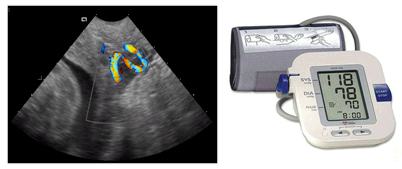

- Cisto anecóico supra-tentorial em linha média, alongado com fluxo arteriovenoso ativo demonstrado pelo color Doppler.

- O defeito se desenvolve no início do primeiro trimestre, mas o aneurisma só se torna aparente à ultrassonografia no terceiro trimestre.

- Em 90% dos casos há insuficiência cardíaca de alto débito e hidropsia secundária.